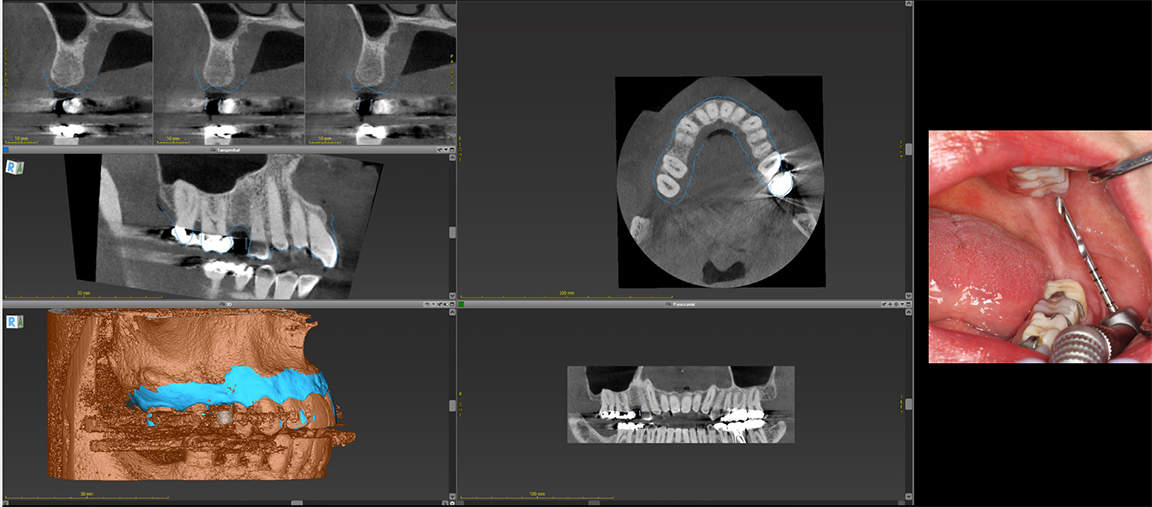

In the case of an edentulous patient, in the virtual surgical planning realm practitioners typically overlay computed tomography (CT) scans for treatment planning purposes and can do so in multiple software platforms (Figure 6). Robotic technology has the same capability to track radiopaque markers, such as gutta percha or global composite.12

The dots between the arches on a CT scan are reference points that are valuable in treatment planning to coordinate data and visualize results to form a blueprint to use in laying the foundation and finding an anatomically correct location for implants (Figure 7). The result is a concerted plan that ends with good results in a predictable manner because the technology allows the practitioner to see everything during planning and surgery. It is not complicated, can happen in the same day, does not involve a protracted treatment planning process, and affords the flexibility to make changes intraoperatively, allowing the practitioner to see where changes would impact not just the patient anatomy, but the prosthetic anatomy.3,4

Fig 6. Practitioners can overlay computed tomography (CT) scans for treatment planning in multiple software platforms.

Figure 6

Fig 7. The dots between the arches on a CT scan are reference points for treatment planning to help coordinate the data and visualize the results before laying the foundation.

Figure 7